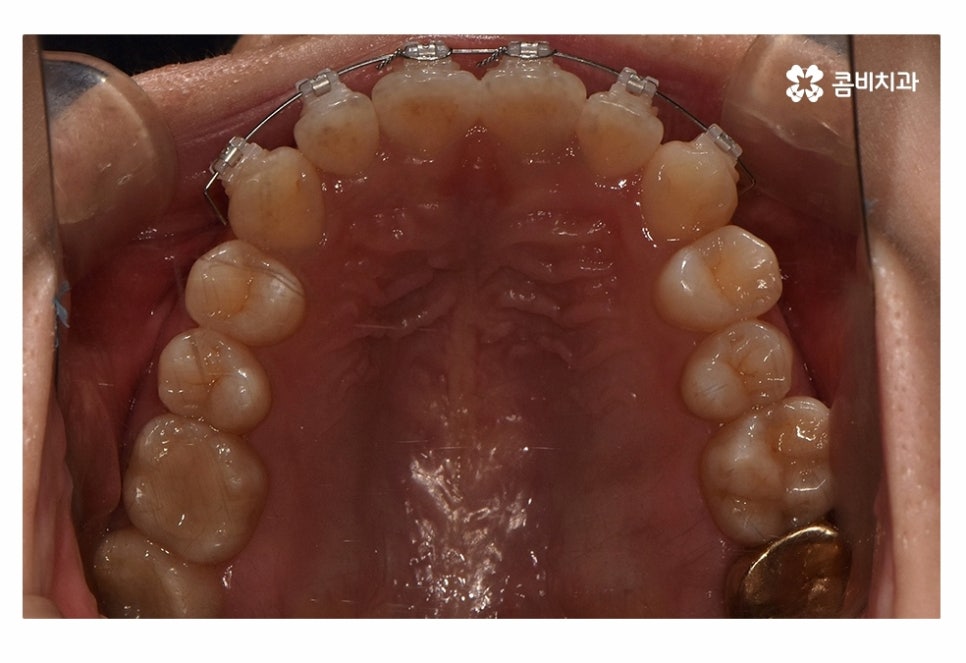

오늘은 치아부분교정 사례와 함께 부분교정에 대한 설명을

해드릴 예정이며 위 사진에서 보시는 환자분의 경우

정면에서 보는 치열과 측면의 차이가 다소 크다는 것을 알 수 있는데요.

위 사진은 치료가 시작되고 약 5개월 정도가 지난 후의 모습인데

치아부분교정으로도 치열이 빠르게 가지런해진 모습을 볼 수 있어요.